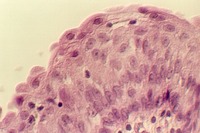

Stratified Cuboidal

Sweat gland ducts are examples of stratified cuboidal epithelium...usually however there are only two layers of cells. They can be found in your slide 25 (thick skin), in the dermis.